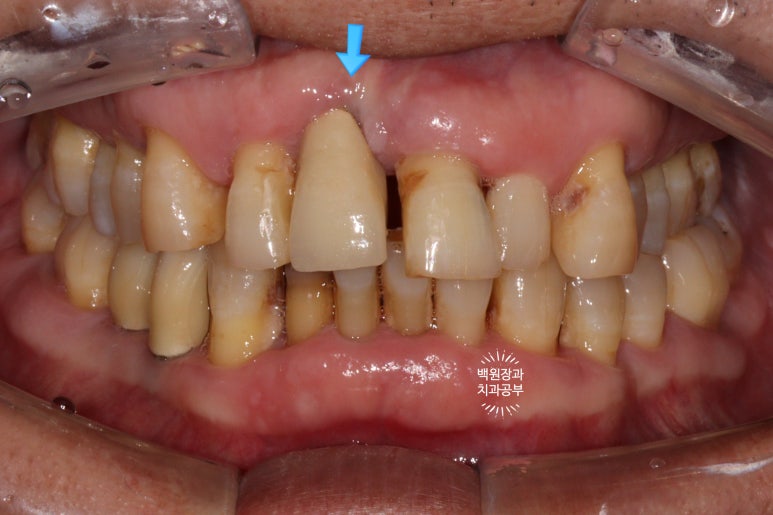

저희 동네 다른 치과에서 (상호는 밝히지 않지만...) 무리하게 앞니 임플란트를 진행하다 뿌리부분인 고정체를 너무 깊게 심어 치아가 상당히 길어져버린 환자분입니다.

매우 비심미적인 결과를 볼 수 있으며, 역시나 매우 불만족 하시고 계셨어요..

그래서 저희 치과에 오시긴 하셨습니다만 이렇게 한 번 잘못 설치된 임플란트는 다시 예쁘게 만들어내기가 불가능하다고 보셔야합니다.

적어도 치료가 끝나면 어떤 모양일지 설명을 들을 수 있고, 그에 따라 어떤 치료 계획을 수립하고 어떻게 진행할지 정확한 상담을 받을 수 있는 치과를 선택하시길 바랍니다.